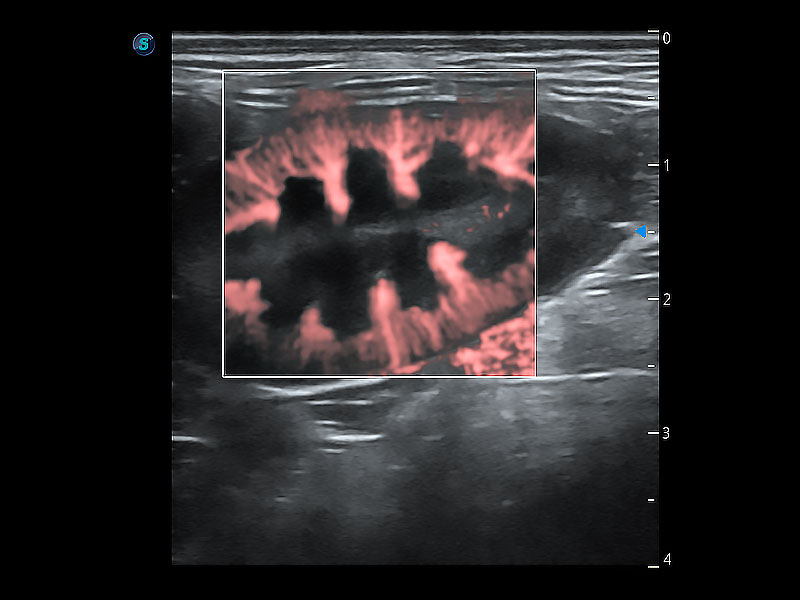

(犬)肾脏显微血流